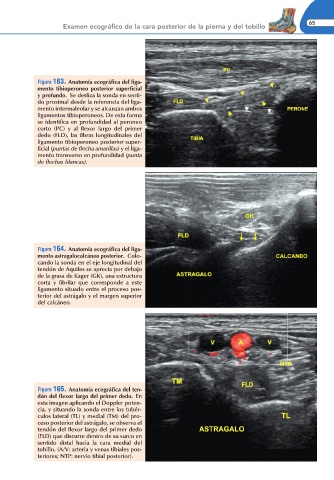

Figura 163. Anatomía ecográ ca del liga-

mento tibioperoneo posterior super cial

y profundo. Se desliza la sonda en senti-

do proximal desde la referencia del liga-

mento intermaleolar y se alcanzan ambos

ligamentos tibioperoneos. De esta forma

se identi ca en profundidad al peroneo

corto (PC) y al exor largo del primer

dedo (FLD), las bras longitudinales del

ligamento tibioperoneo posterior super-

cial (puntas de echa amarillas) y el liga-

mento transverso en profundidad (punta

de echas blancas).

Figura 164. Anatomía ecográ ca del liga-

mento astragalocalcáneo posterior. Colo-

cando la sonda en el eje longitudinal del

tendón de Aquiles se aprecia por debajo

de la grasa de Kager (GK), una estructura

corta y brilar que corresponde a este

ligamento situado entre el proceso pos-

terior del astrágalo y el margen superior

del calcáneo.

Figura 165. Anatomía ecográ ca del ten-

dón del exor largo del primer dedo. En

esta imagen aplicando el Doppler poten-

cia, y situando la sonda entre los tubér-

culos lateral (TL) y medial (TM) del pro-

ceso posterior del astrágalo, se observa el

tendón del exor largo del primer dedo

(FLD) que discurre dentro de su surco en

sentido distal hacia la cara medial del

tobillo. (A/V: arteria y venas tibiales pos-

teriores; NTP: nervio tibial posterior).